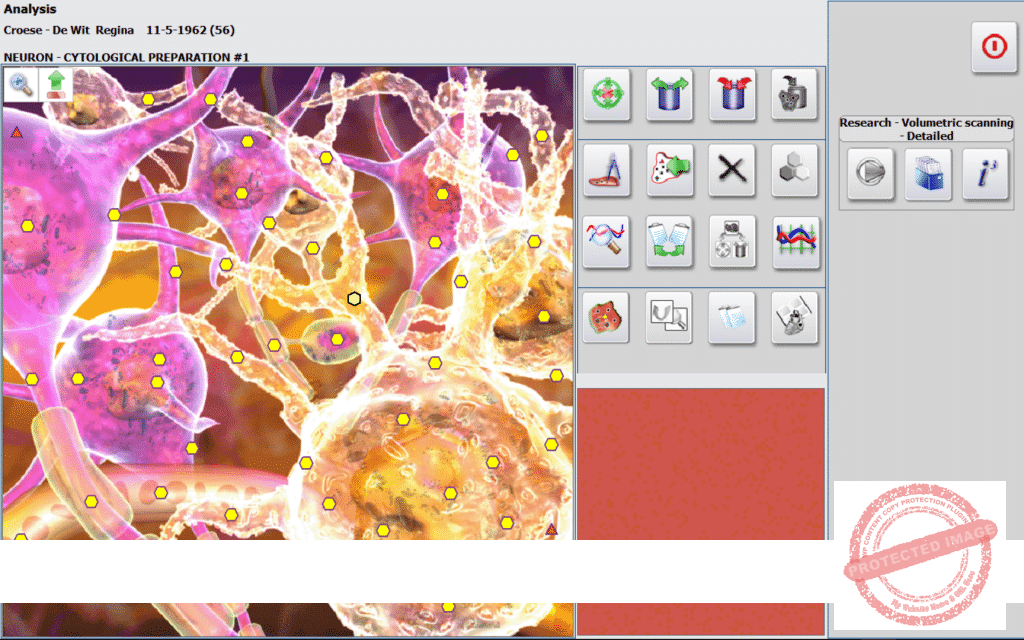

*A preview of The ISHA METATRON PRO, the most powerful for microscopic INDEPTH scans and treatments